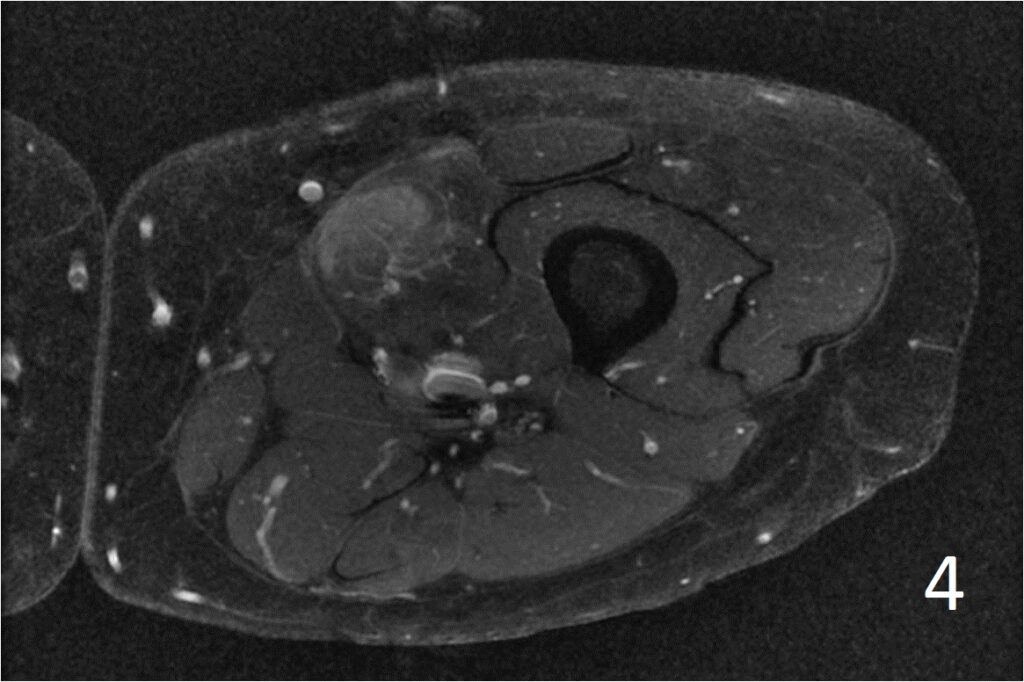

MRI

• Well defined heterogeneous mass on T1W and IR sequences (Fig. 2, 3) heterogeneous enhancement on postcontrast images (Fig. 4)

Fig. 2-4: Axial T1W FS of the thigh shows a ill-defined mass in medial thigh, and fairly well defined and heterogeneous on IR sequence (Fig. 3). Axial T1W displays a heterogeneous mass with mild enhancement post gadolinium (Fig. 4)